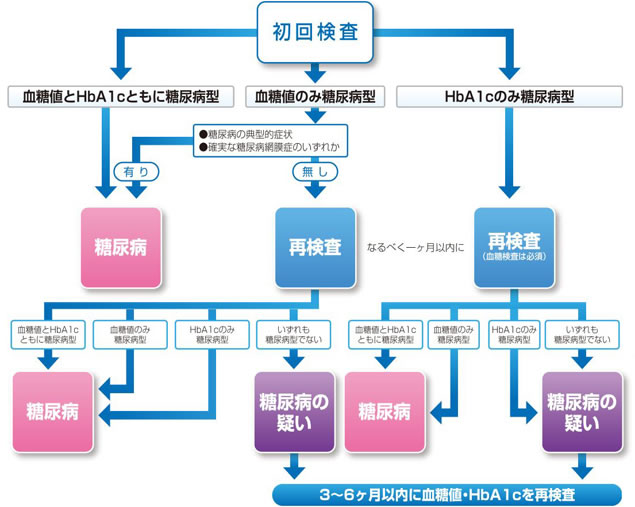

糖尿病:

糖尿病患者は、統計的に歯周疾患を既往している率が高く、糖尿病併発症として歯周疾患は6番目に位置付けられています。

【血糖値】

①空腹時血糖値≧126mg/dL

②75g経口糖負荷試験(OGTT)2時間値≧200mg/dL

③随時血糖値≧200mg/dL

【HbA1c】

④HbA1c(NGSP)≧6.5%

糖尿病が歯周病を含めた感染症を悪化させることはよく知られていますが、歯周病も糖尿病を悪化させます。歯周病の治療・管理により1型・2型を含めた糖尿病患者では、歯周病の治療を行うことでHbA1cが平均0.4%改善するという報告もあります。

副院長は日本糖尿病協会 歯科医師登録医ですので、なんでも相談してください。